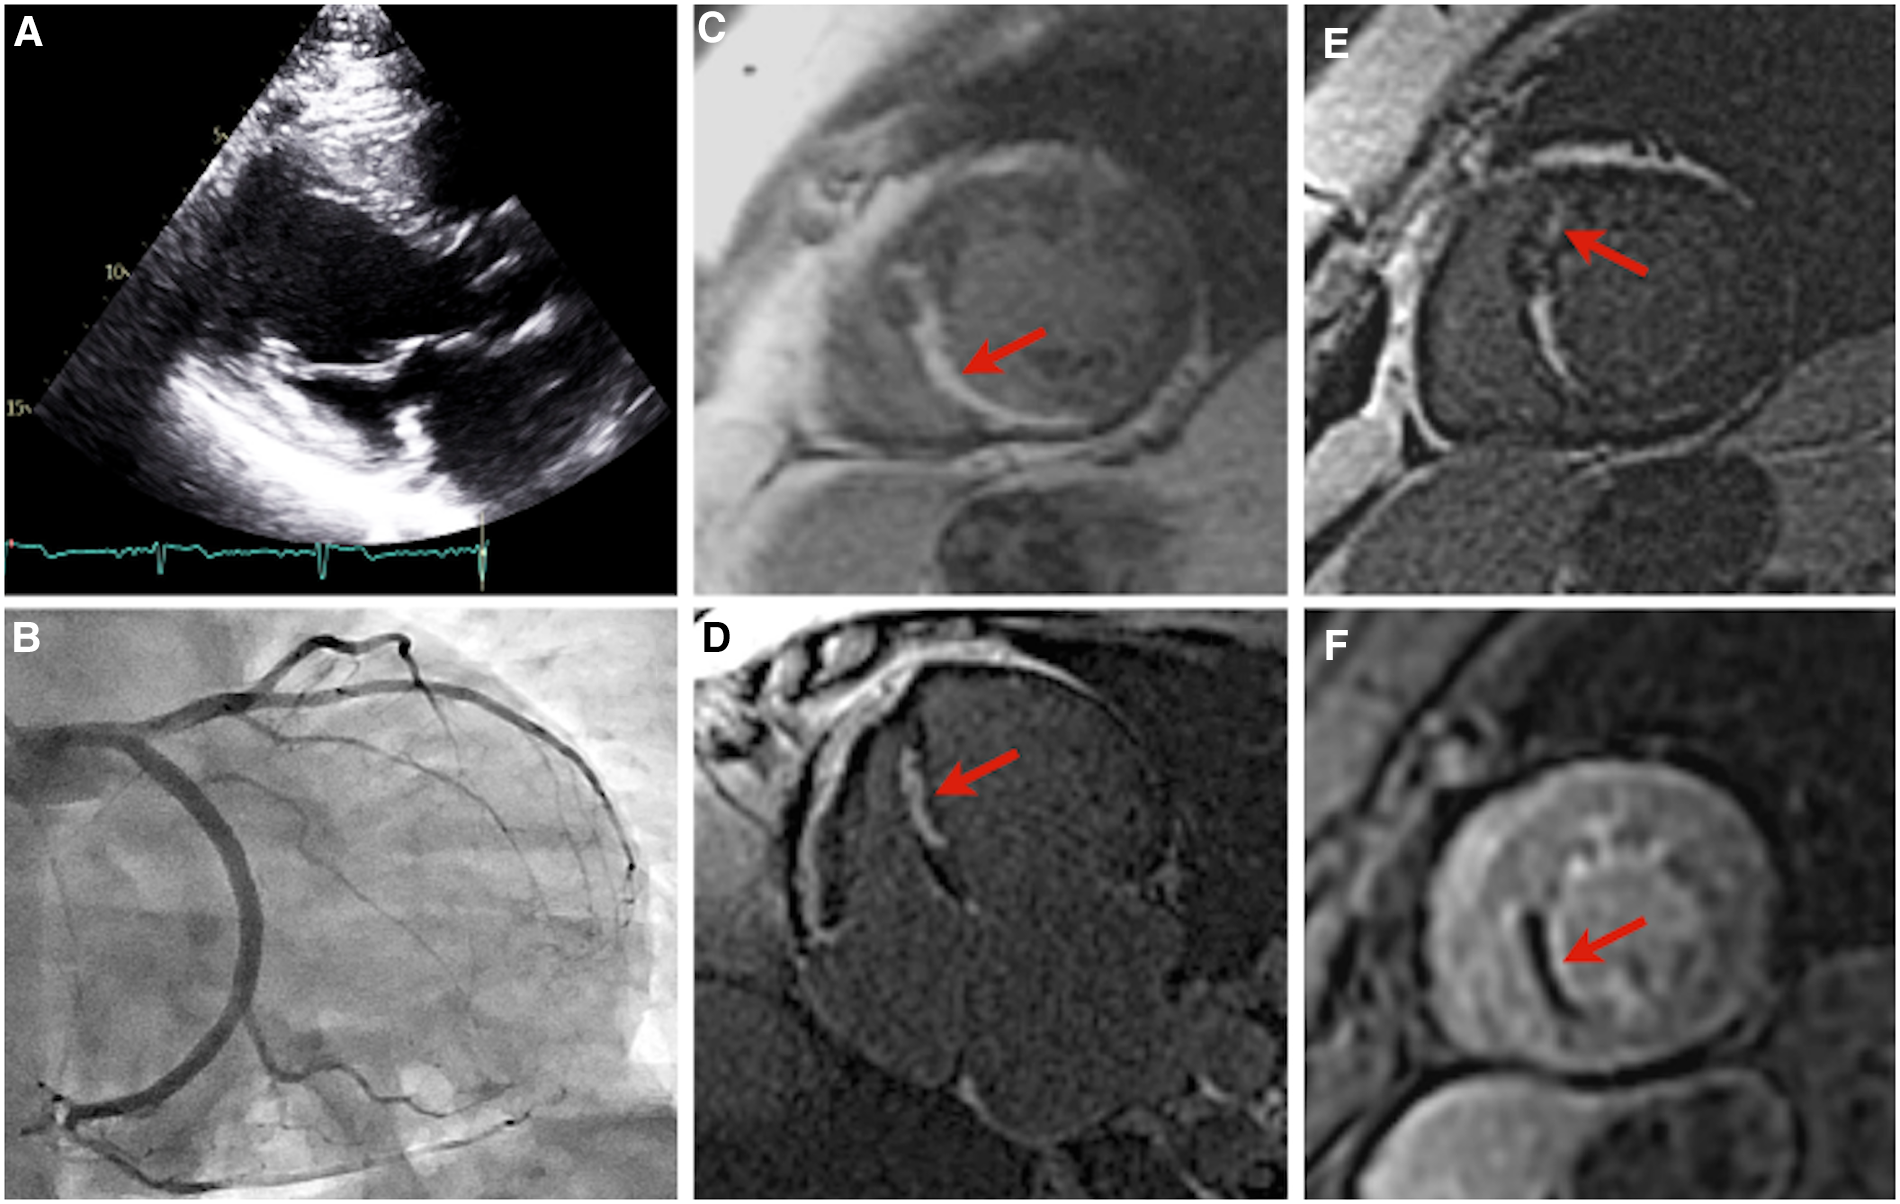

Figure 3

Imaging of patient B. Parasternal long axis echocardiogram, with an interventricular septal thickness measurement of 11 mm during diastole, and a patent left ventricular outflow tract (A). Right anterior oblique caudal angiogram demonstrating a diminutive left anterior descending artery (B). Images (C–F): cardiac magnetic resonance imaging of patient B. Near-transmural delayed gadolinium enhancement of the mid inferior and inferoseptal wall segments, short-axis view (C). Near-transmural delayed gadolinium enhancement of the mid inferior and inferoseptal wall segments, four-chamber view (D). Focus of mid-myocardial delayed gadolinium enhancement in the mid anteroseptal wall segment, short-axis view (E). Near-transmural septal hypoperfusion, short-axis view (F).

Patient B was first referred at age 46 for genetic evaluation shortly after patient A began workup for HCM, as per familial screening guidelines, and was revealed to be a carrier of the pathogenic TNNT2 variant. Her initial transthoracic echocardiogram revealed a maximal wall thickness of 11 mm with hypokinesis in the basal to mid inferior wall and basal to mid anteroseptal walls, with no evidence of obstruction (Figure 3A). ECG demonstrated baseline ST and T wave abnormalities. Prior to this evaluation she had experienced chronic episodic chest pain without other cardiac symptoms or clear precipitating factors, though cardiac diagnostic evaluation had never been pursued. Holter monitoring revealed a 7-beat run of nonsustained ventricular tachycardia at 129 bpm. A treadmill stress echocardiogram with maximal exertion resulted in no symptoms of chest pain. Electrocardiographic findings were within normal limits aside from baseline ST and T wave abnormalities. There was normal augmentation of left ventricular function with an increase in ejection fraction from 55% at rest to 65% during peak stress. No new regional wall motion abnormalities were identified. No further coronary evaluation was pursued.

She remained well from a cardiovascular standpoint until 8 years thereafter, when she presented to an outside emergency department with palpitations and intermittent chest discomfort. Newly identified atrial tachycardia was present with a ventricular rate of 130–150 bpm. She developed significant bradycardia (30 s bpm) with first-degree AV block after 3.5 mg of intravenous metoprolol tartrate. Her troponin I level was also noted to be mildly elevated to 1.352 ng/ml (reference range ≤0.013 ng/ml) and NT-proBNP to 260 pg/ml (reference ≤100 pg/ml). Coronary angiography revealed normal variant anatomy with a diminutive LAD (Figure 3B). She was monitored overnight with no further tachyarrhythmia or chest discomfort and discharged on dual anti-platelet therapy and high-intensity statin therapy.

Subsequent outpatient cardiac MRI demonstrated wall thinning and akinesia of the mid inferior and inferior septal segments with near transmural delayed enhancement hypoperfusion, and focal myocardial delayed enhancement of the mid anterior septal wall segment (Figures 3C–F). Repeat transthoracic echocardiography demonstrated a severely enlarged left atrium, left ventricular ejection fraction 54%, and ventricular septal thickness of 11 mm. Ambulatory Holter monitoring thereafter demonstrated low ectopic burden with self-limiting runs of atrial tachycardia and two 4-beat runs of nonsustained ventricular tachycardia.

Patient B had milder LV hypertrophy with evidence of microvascular angina. Overall, her presentation was more consistent with the typical phenotype seen in thin-filament HCM (17, 18). She had no functional limitations in her daily life and remained relatively asymptomatic until presenting to the emergency department with palpitations. Serial lab work in the outpatient setting revealed a chronically elevated baseline troponin level, consistent with HCM (19). Together, these findings suggest HCM rather than an acute infarct as the cause of her initial presentation. The pattern of patchy mid-wall late gadolinium enhancement involving the interventricular septum observed on her MR imaging (Figures 3C–E) is attributable to myocardial fibrosis and occurs in approximately 60% of HCM patients with LVH (20). A similar distribution of late gadolinium enhancement was previously documented in another p.Arg92Gln-TNNT2-positive individual who presented without symptoms or echocardiographic evidence of HCM (21). The functional implications of late gadolinium enhancement in the setting of HCM remain unclear. Previous studies have found it to be inconsequential, whereas others have demonstrated associations with increased myocardial stiffness, regional wall motion abnormalities, and diminished LV systolic function (20). Regions of fibrosis may also serve as arrhythmogenic substrates and the extent of scarring has been correlated with sudden cardiac death and major adverse cardiovascular events (21, 22). Because of this, the 2020 ACC/AHA guidelines have highlighted the clinical utility of late gadolinium enhancement evaluation in HCM sudden cardiac death risk stratification (23).